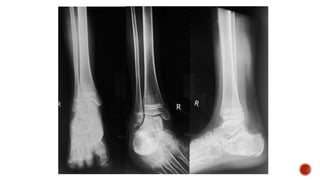

 Radiographic views for ankle joint

 Ankle farcture/dislocation

 Talus involvement

 Osteoarthritis ankle

•The leg must be rotated internally 15° to 20°, thus aligning the

intermalleolar line parallel to the detector. This usually results in the

5th toe being directly in line with the center of the calcaneum